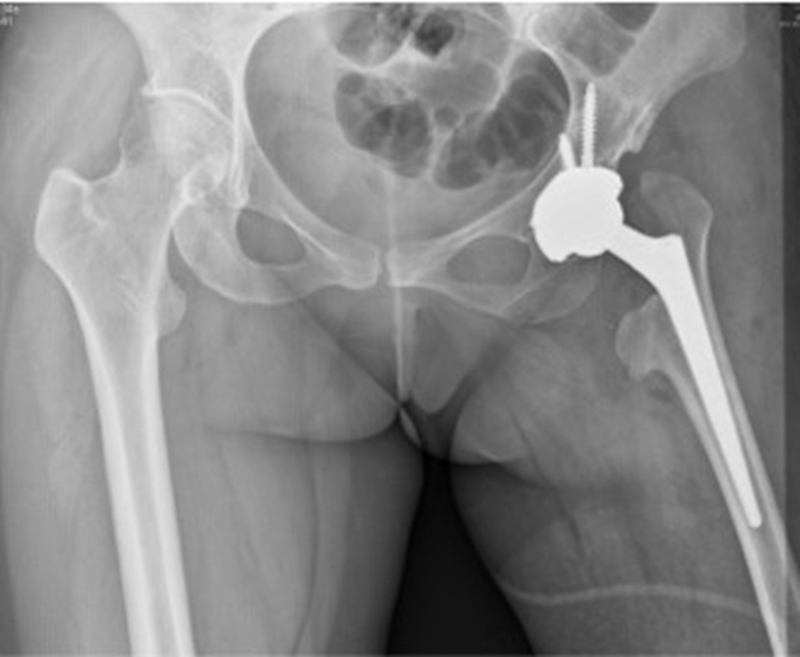

③近端的重建:纠正性截骨,短缩截骨。

纠正性截骨的要求是:

①在畸形最严重的部位纠正对线不良;

②最大限度保留骨质;

③截骨部位牢固固定;

④使用长柄假体跨越截骨端。

股骨截骨的不同方法:

股骨近端截骨重建——截骨方式:横形、斜形、阶梯式及双V形截骨

优点:不改变股骨近端的解剖,保持臀中肌附丽点完整,截骨后能矫正股骨的前倾角,是较为理想的股骨缩短方法。

缺点:①骨折——截骨两端捆钢丝;②截骨端不稳定,术后骨折不愈合——足够长的远端固定型非骨水泥型假体或组配型假体,假体长度足够,避免型号过小,必要时使用骨板加强固定;③失血多、时间长。